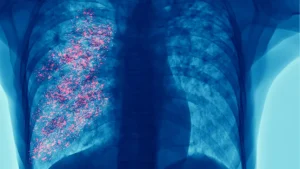

El cáncer de pulmón es responsable de 1.8 millones de muertes al año, más que cualquier otro tipo de cáncer. En Panamá, se registran 370 casos nuevos y más de 300 defunciones cada año, representando el 8.1% de los diagnósticos oncológicos.

Su letalidad se explica porque el 85% de los casos se diagnostica en etapas avanzadas, cuando el tumor ya ha metastatizado. Solo el 15% se identifica temprano, con una tasa de supervivencia a cinco años superior al 60%.